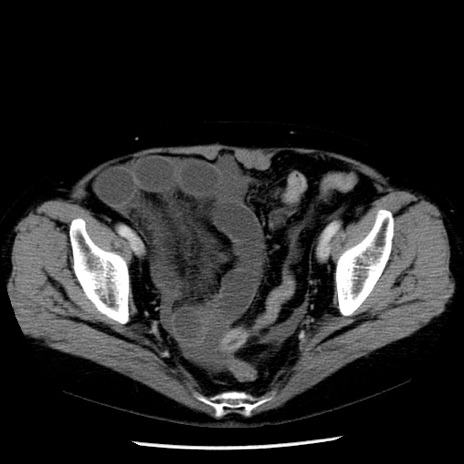

症例13(横断像)

【症例】70歳代女性

【主訴】腹痛、嘔吐

【現病歴】15時間程前(昨晩)より腹痛あり。今朝になっても症状の改善なく、嘔吐あり。腹痛も増悪あり、救急外来受診。

【既往歴】子宮癌全摘術後

【身体所見】意識清明、BP 121/72mmHg、P 74bpm、SpO2 100%(RA)、腹部:平坦・軟、腸雑音ほぼ聴取せず。下腹部・心窩部・臍左上に圧痛あり。反跳痛なし。

【データ】WBC 10600、CRP 0.15